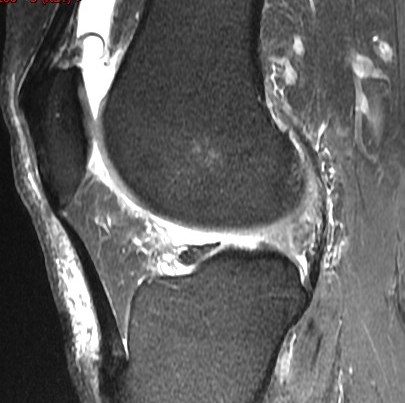

72 y/o M with all over knee pain. No known trauma. R/O meniscus tear.

Root attachment tear of the posterior horn of the lateral meniscus (RID2763)

Much more common to see these medially. These can be mimicked by magic angle but magic angle alone wont result in the irregularity seen here. Also there is some peripheral subluxation of the meniscus suggesting instability. Lateral root tears commonly occur with knee ligament sprains and tears. This patient had a chronic partial tear of the ACL (not shown) Reference article.